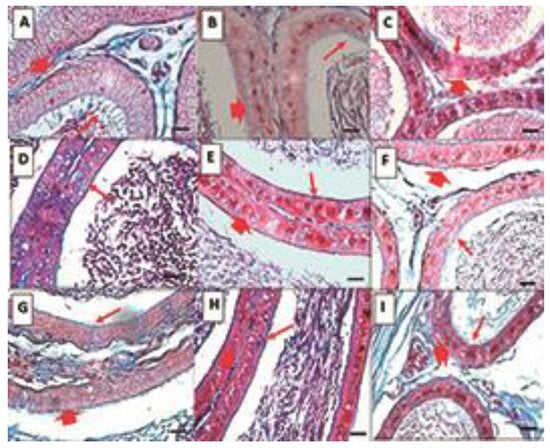

2.4. Histological Analysis

Testicle

- Epididymis